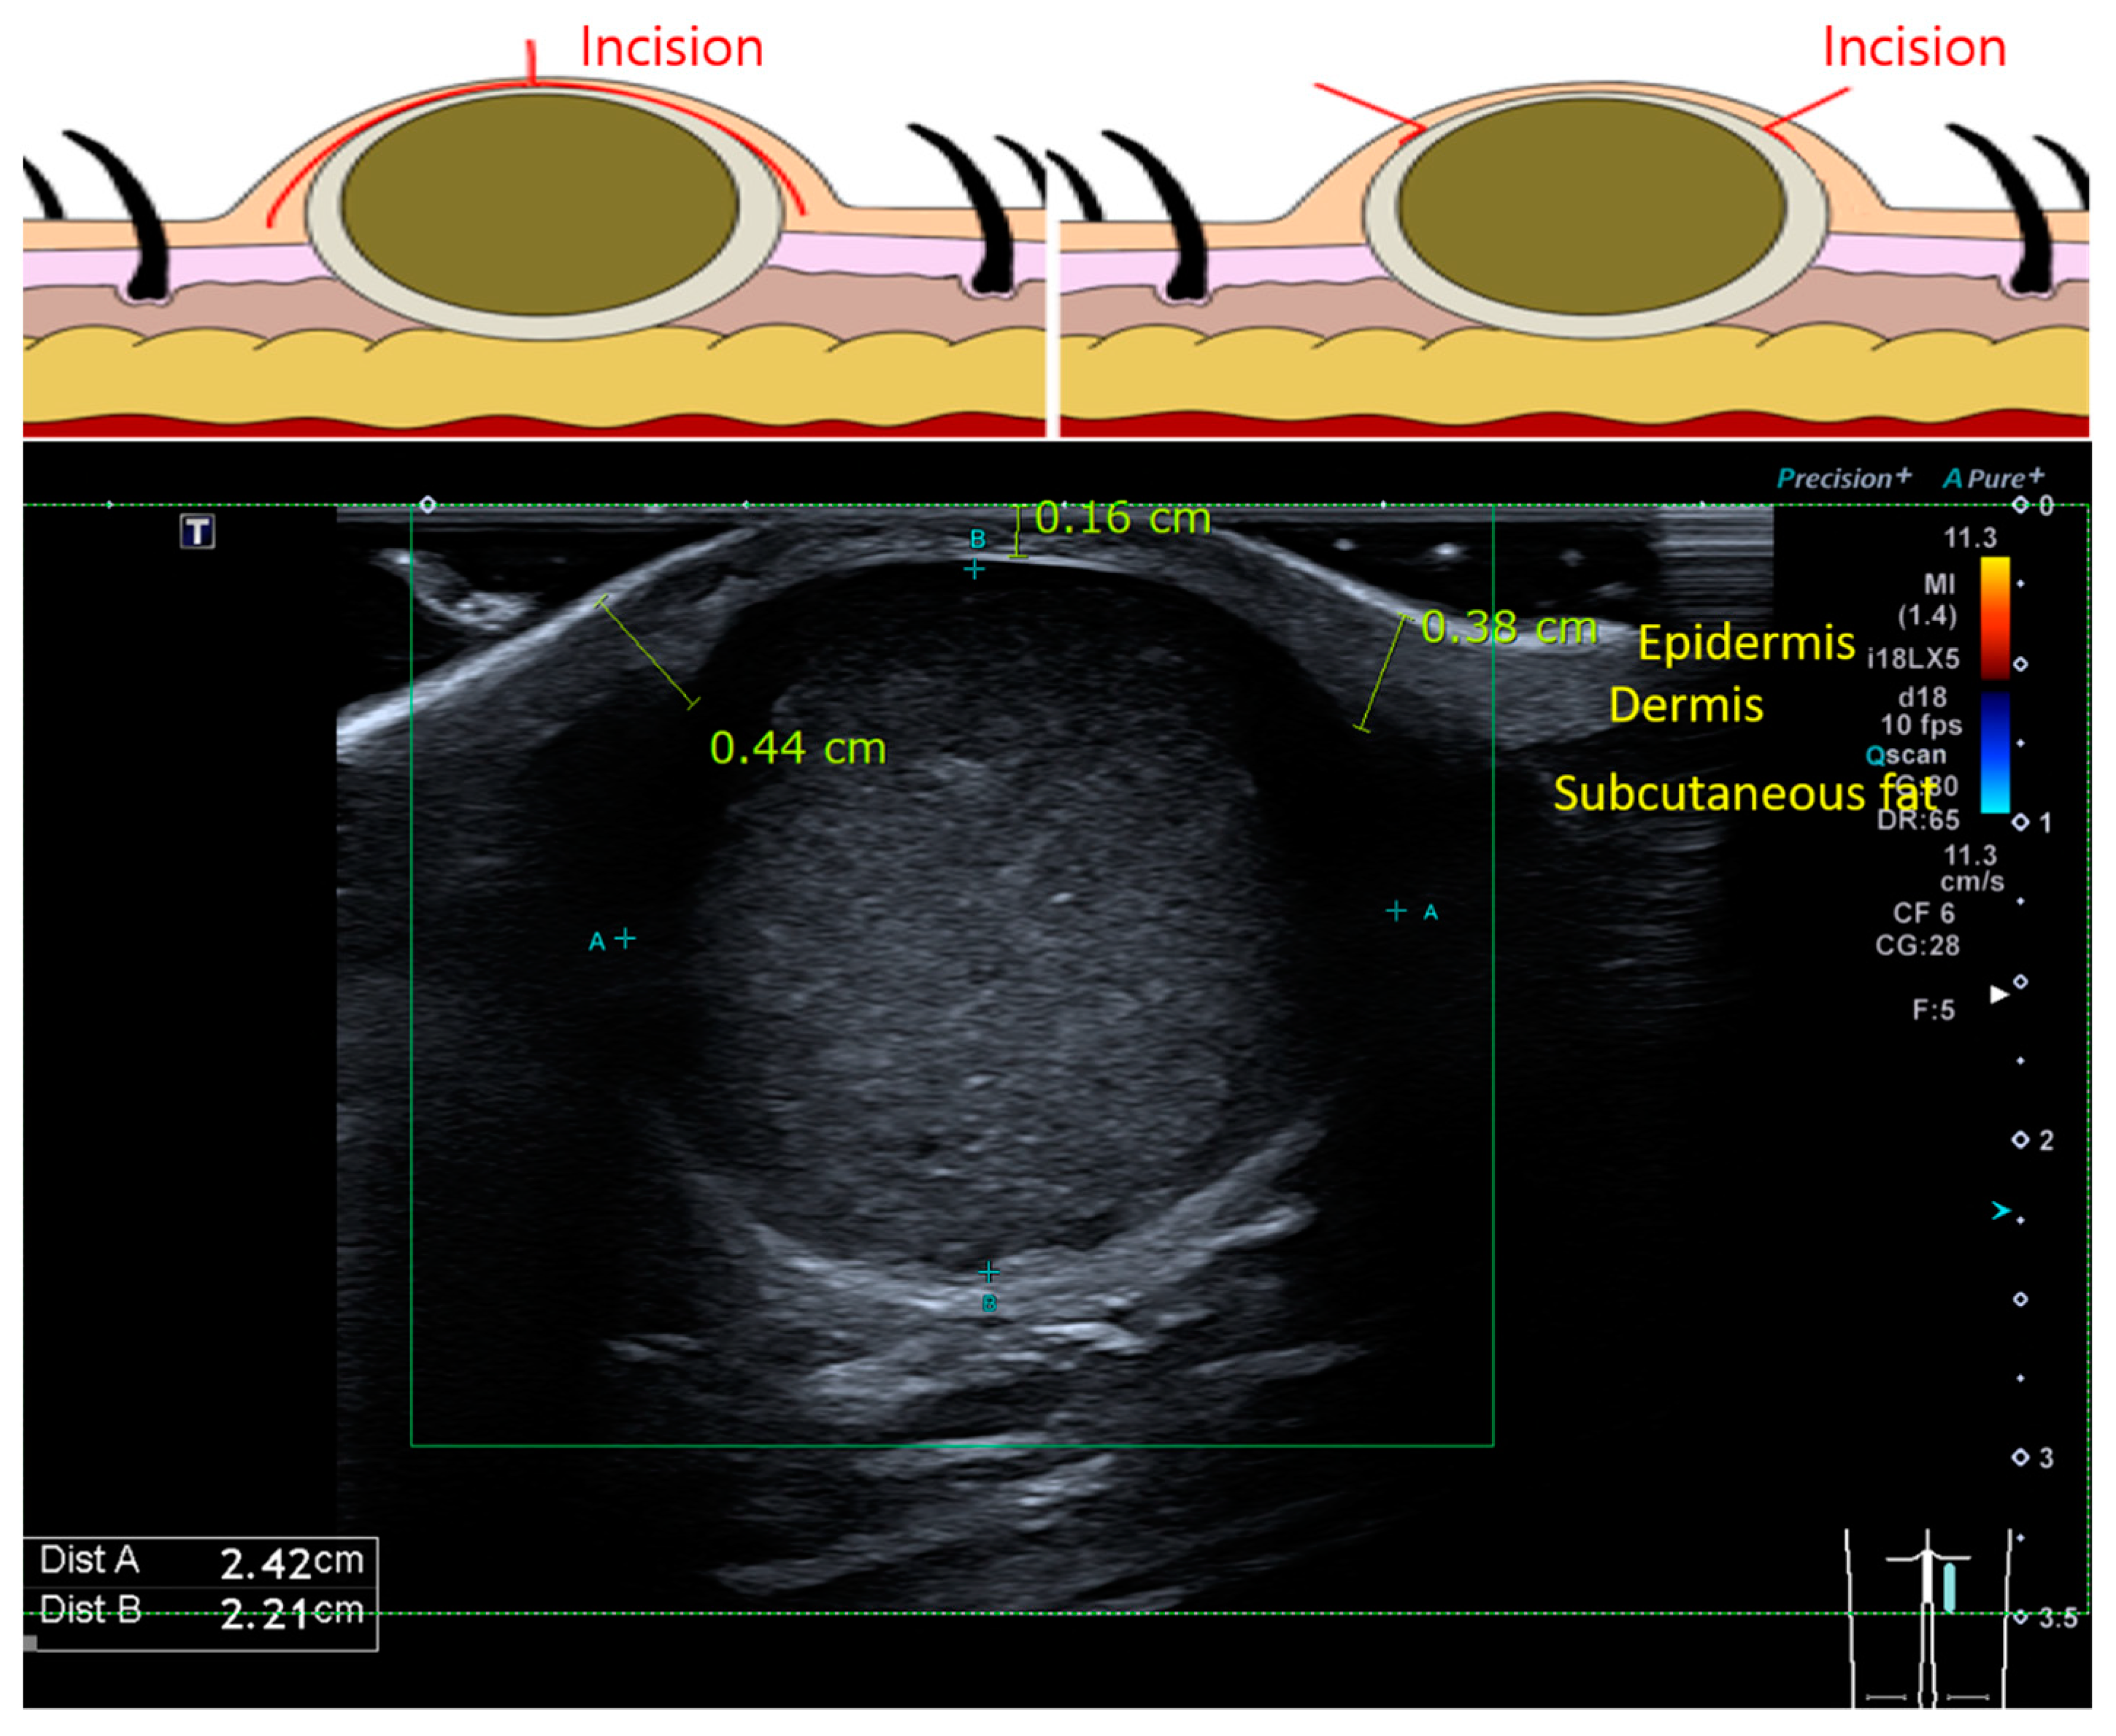

1. Introduction

2.1. Patient Selection and Surgical Methods